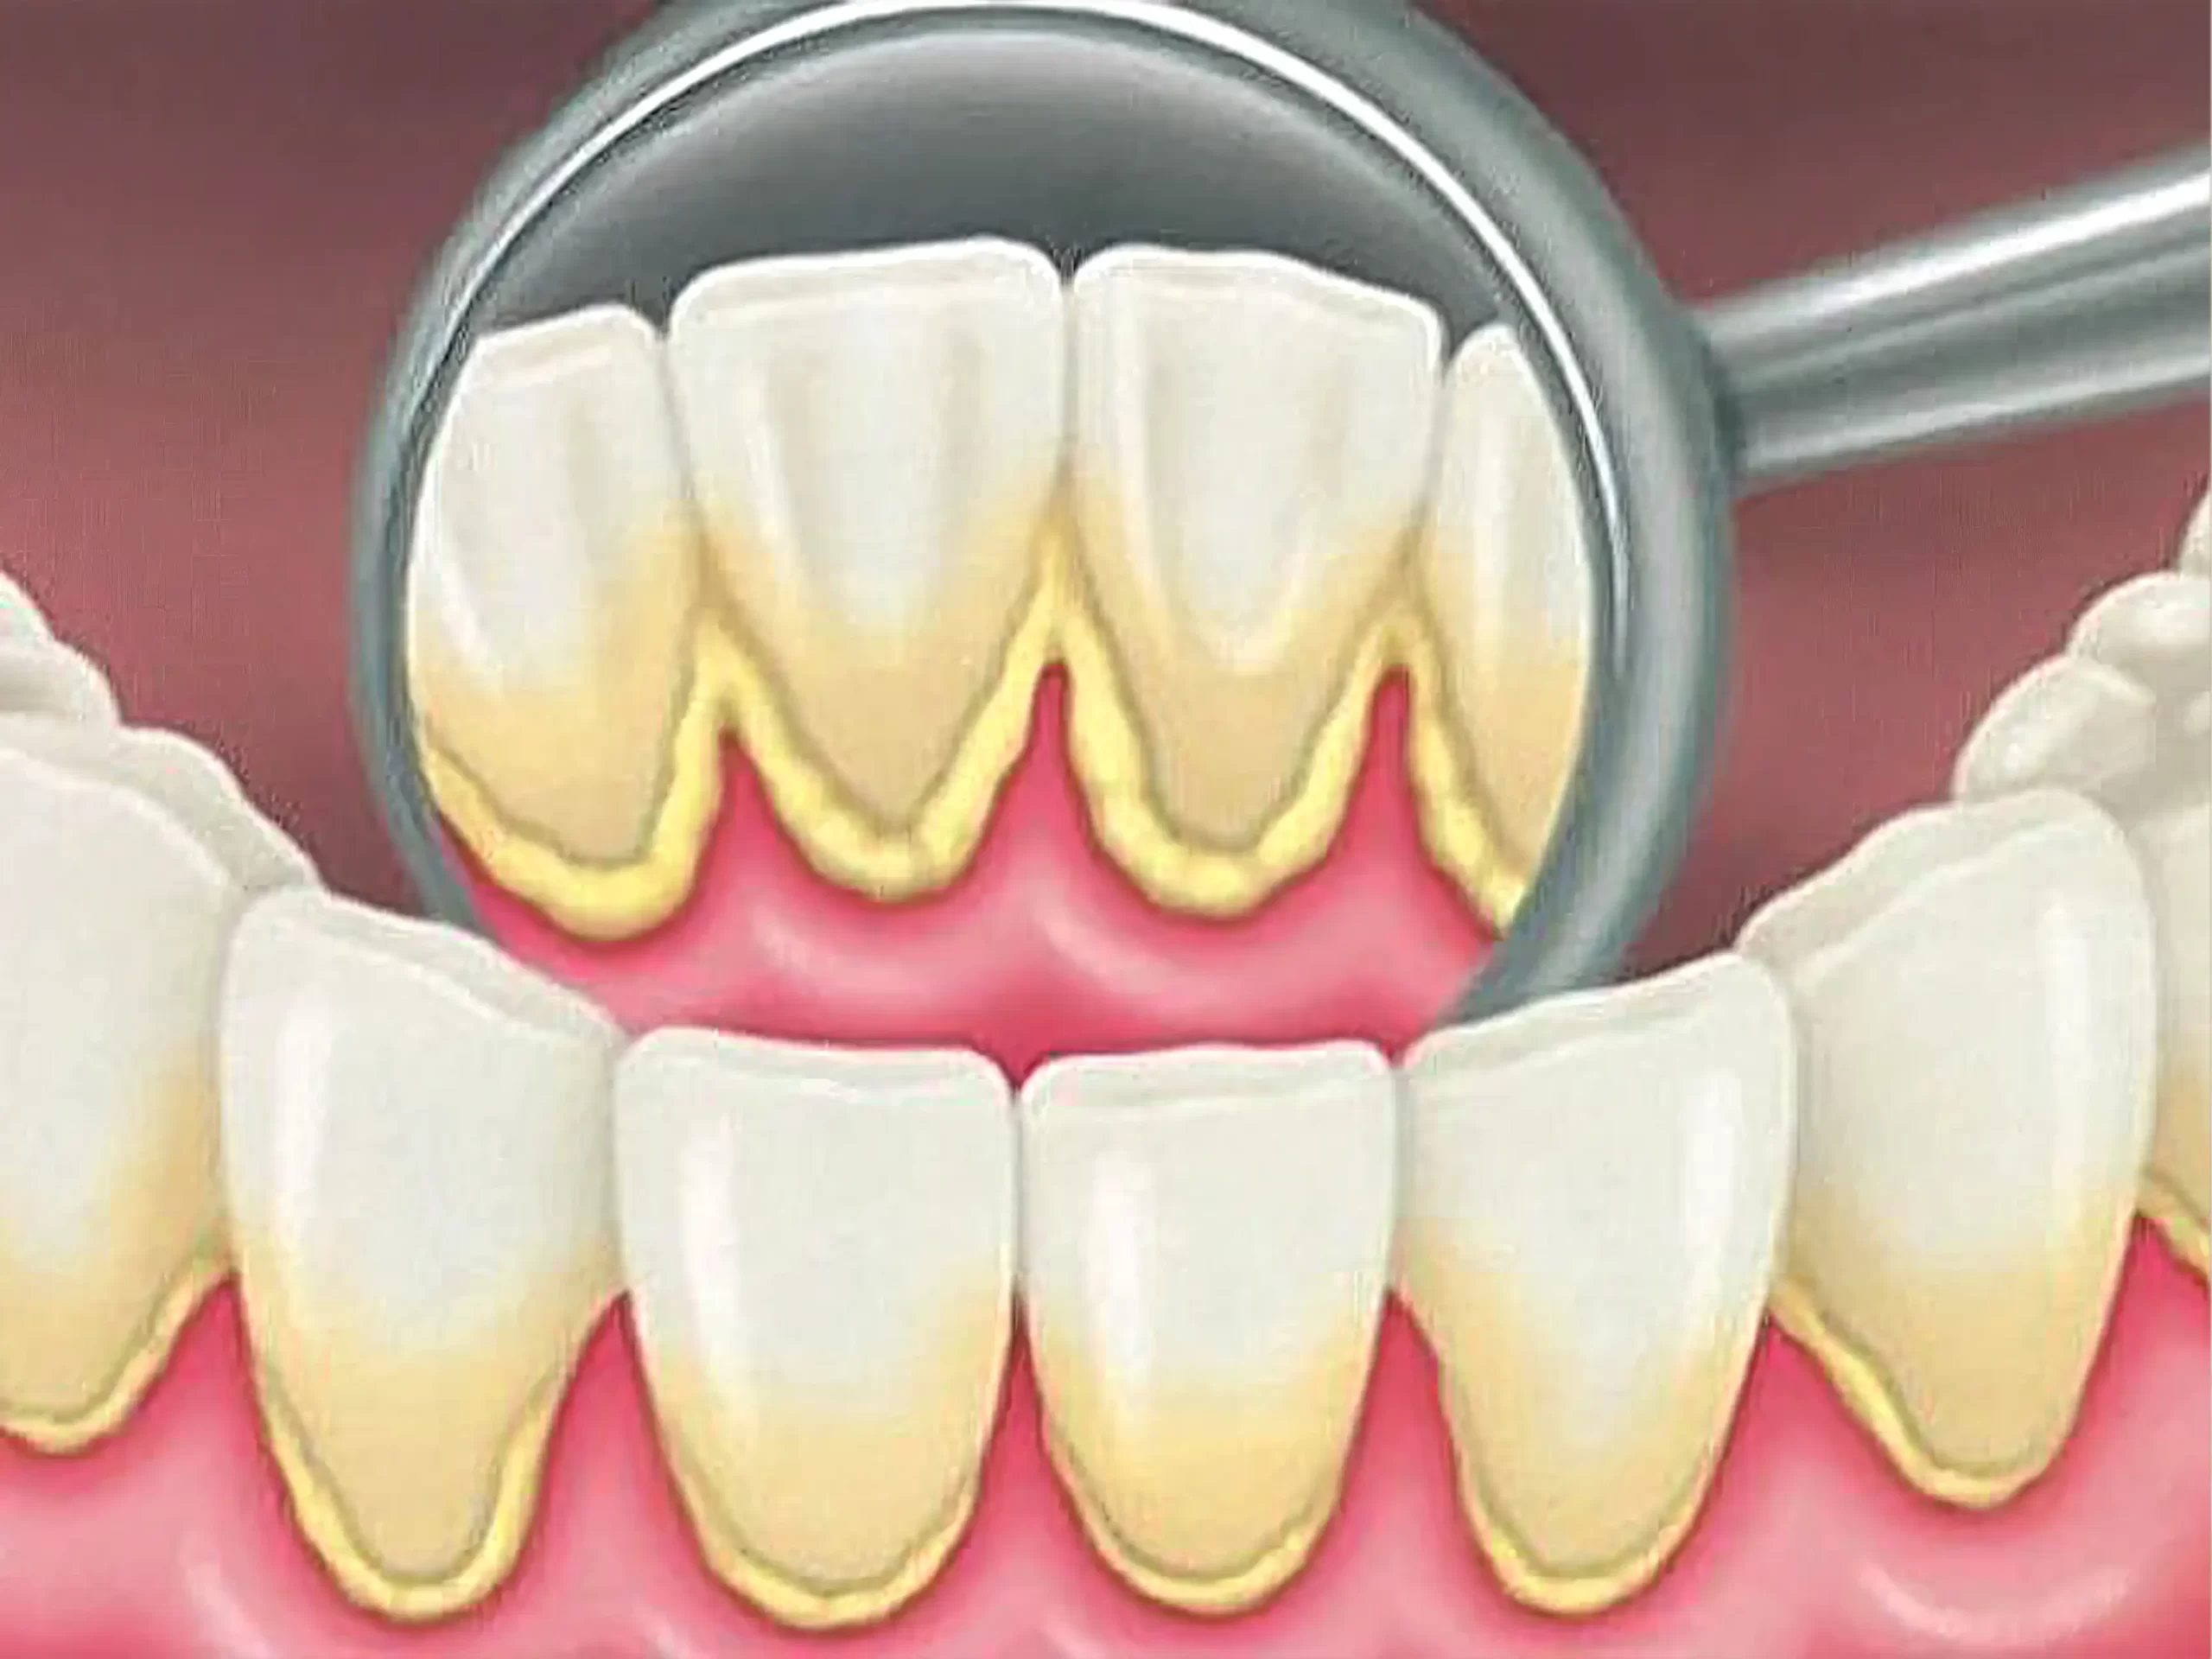

Cặn thức ăn và vi khuẩn tích tụ lâu ngày sẽ tạo thành mảng bám, sau đó khoáng hóa thành cao răng. Cao răng thường có màu vàng nâu hoặc đen, bám chặt ở răng hàm – nơi khó vệ sinh.

Một số bệnh lý như viêm nướu, viêm nha chu hay tổn thương men răng cũng khiến răng có vết đen.

- Lấy cao răng và đánh bóng: Đây là bước cơ bản và cần thiết. Việc loại bỏ mảng bám và cao răng cứng đầu giúp loại bỏ vết ố đen do vi khuẩn hoặc khoáng hóa. Sau đó, đánh bóng sẽ làm mịn bề mặt răng, giảm khả năng bám dính của các chất tạo màu.